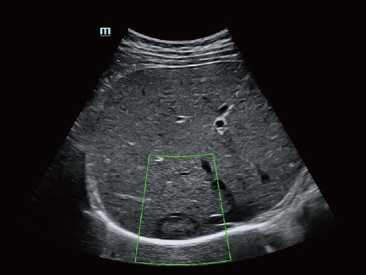

UWN+?(–љ–µ–ї–Є–љ–µ–є–љ–∞—П –≤–Є–Ј—Г–∞–ї–Є–Ј–∞—Ж–Є—П –≤ —Г–ї—М—В—А–∞—И–Є—А–Њ–Ї–Њ–Љ –і–Є–∞–њ–∞–Ј–Њ–љ–µ) –і–ї—П –Ї–Њ–љ—В—А–∞—Б—В–љ–Њ–є —Н—Е–Њ–≥—А–∞—Д–Є–Є –њ–Њ–Ј–≤–Њ–ї—П–µ—В —Б–Є—Б—В–µ–Љ–µ Resona 6 –Њ–±–љ–∞—А—Г–ґ–Є–≤–∞—В—М –Є –Є—Б–њ–Њ–ї—М–Ј–Њ–≤–∞—В—М –Ї–∞–Ї –≤—В–Њ—А—Л–µ –≥–∞—А–Љ–Њ–љ–Є–Ї–Є, —В–∞–Ї –Є –љ–µ–ї–Є–љ–µ–є–љ—Л–µ –њ–µ—А–≤–Є—З–љ—Л–µ —Б–Є–≥–љ–∞–ї—Л. –Ґ–µ—Е–љ–Њ–ї–Њ–≥–Є—П –њ–Њ–Ј–≤–Њ–ї—П–µ—В —Б–Њ–Ј–і–∞–≤–∞—В—М –Є–Ј–Њ–±—А–∞–ґ–µ–љ–Є—П –Ї–Њ–љ—В—А–∞—Б—В–љ–Њ–є —Н—Е–Њ–≥—А–∞—Д–Є–Є –±–Њ–ї–µ–µ –≤—Л—Б–Њ–Ї–Њ–≥–Њ –Ї–∞—З–µ—Б—В–≤–∞ —Б –±–Њ–ї—М—И–µ–є —З—Г–≤—Б—В–≤–Є—В–µ–ї—М–љ–Њ—Б—В—М—О –Ї–Њ –≤—В–Њ—А–Њ—Б—В–µ–њ–µ–љ–љ—Л–Љ —Б–Є–≥–љ–∞–ї–∞–Љ, –±–Њ–ї—М—И–Є–Љ –≤—А–µ–Љ–µ–љ–µ–Љ –і–µ–є—Б—В–≤–Є—П –∞–Ї—В–Є–≤–љ–Њ–≥–Њ –≤–µ—Й–µ—Б—В–≤–∞ –Є –±–Њ–ї–µ–µ –љ–Є–Ј–Ї–Є–Љ–Є —В—А–µ–±–Њ–≤–∞–љ–Є—П–Љ–Є –Ї –Є–љ—В–µ—А–≤–∞–ї—Г –Є–Ј–Љ–µ—А–µ–љ–Є—П.